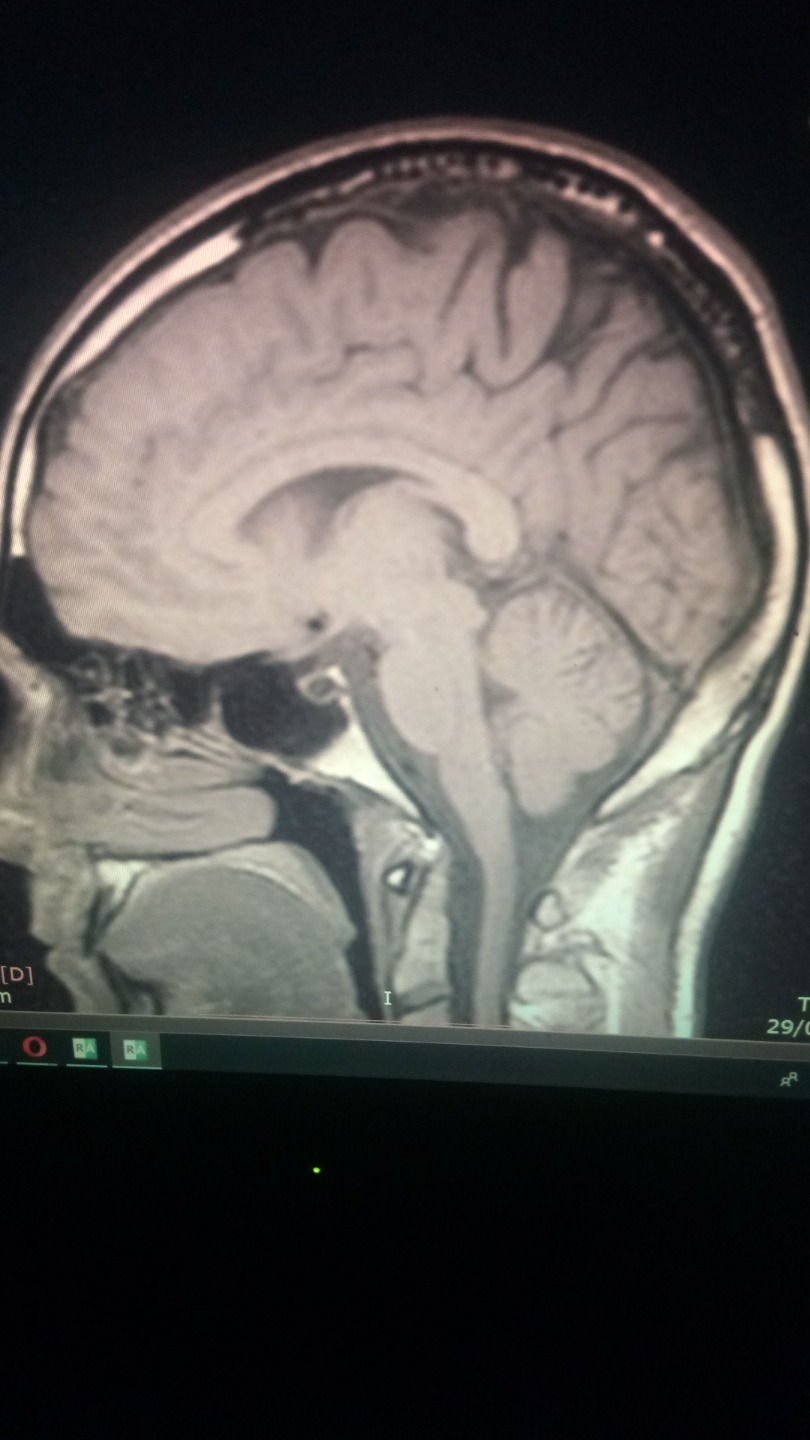

PD : Will atach a photo of my brain, if anyone knows how to read mri scans and know what is going on on my brain is real apreciated. I just think is a infection that somehow is cicatrized thanks to mms.

Neurologist says I have nothin, I dont believe him.

the infection ( look at the pics of my brain mri, i had not headaches, nor nothing, but my brain was having an infections, i noticed something was wrong because i had insomnia for 3 months , like real hardcore insmonia, visual snow, poor memory and concentration, joint paints, dificulti breathing (babesia like simptom) coughfin, and stuff like that. But it wasnt like a normal type of cold. It was weird. I got headeaches when I started to take mms, specially big doses of 15 drops. less than that and standart protocol 1000 was not effective.